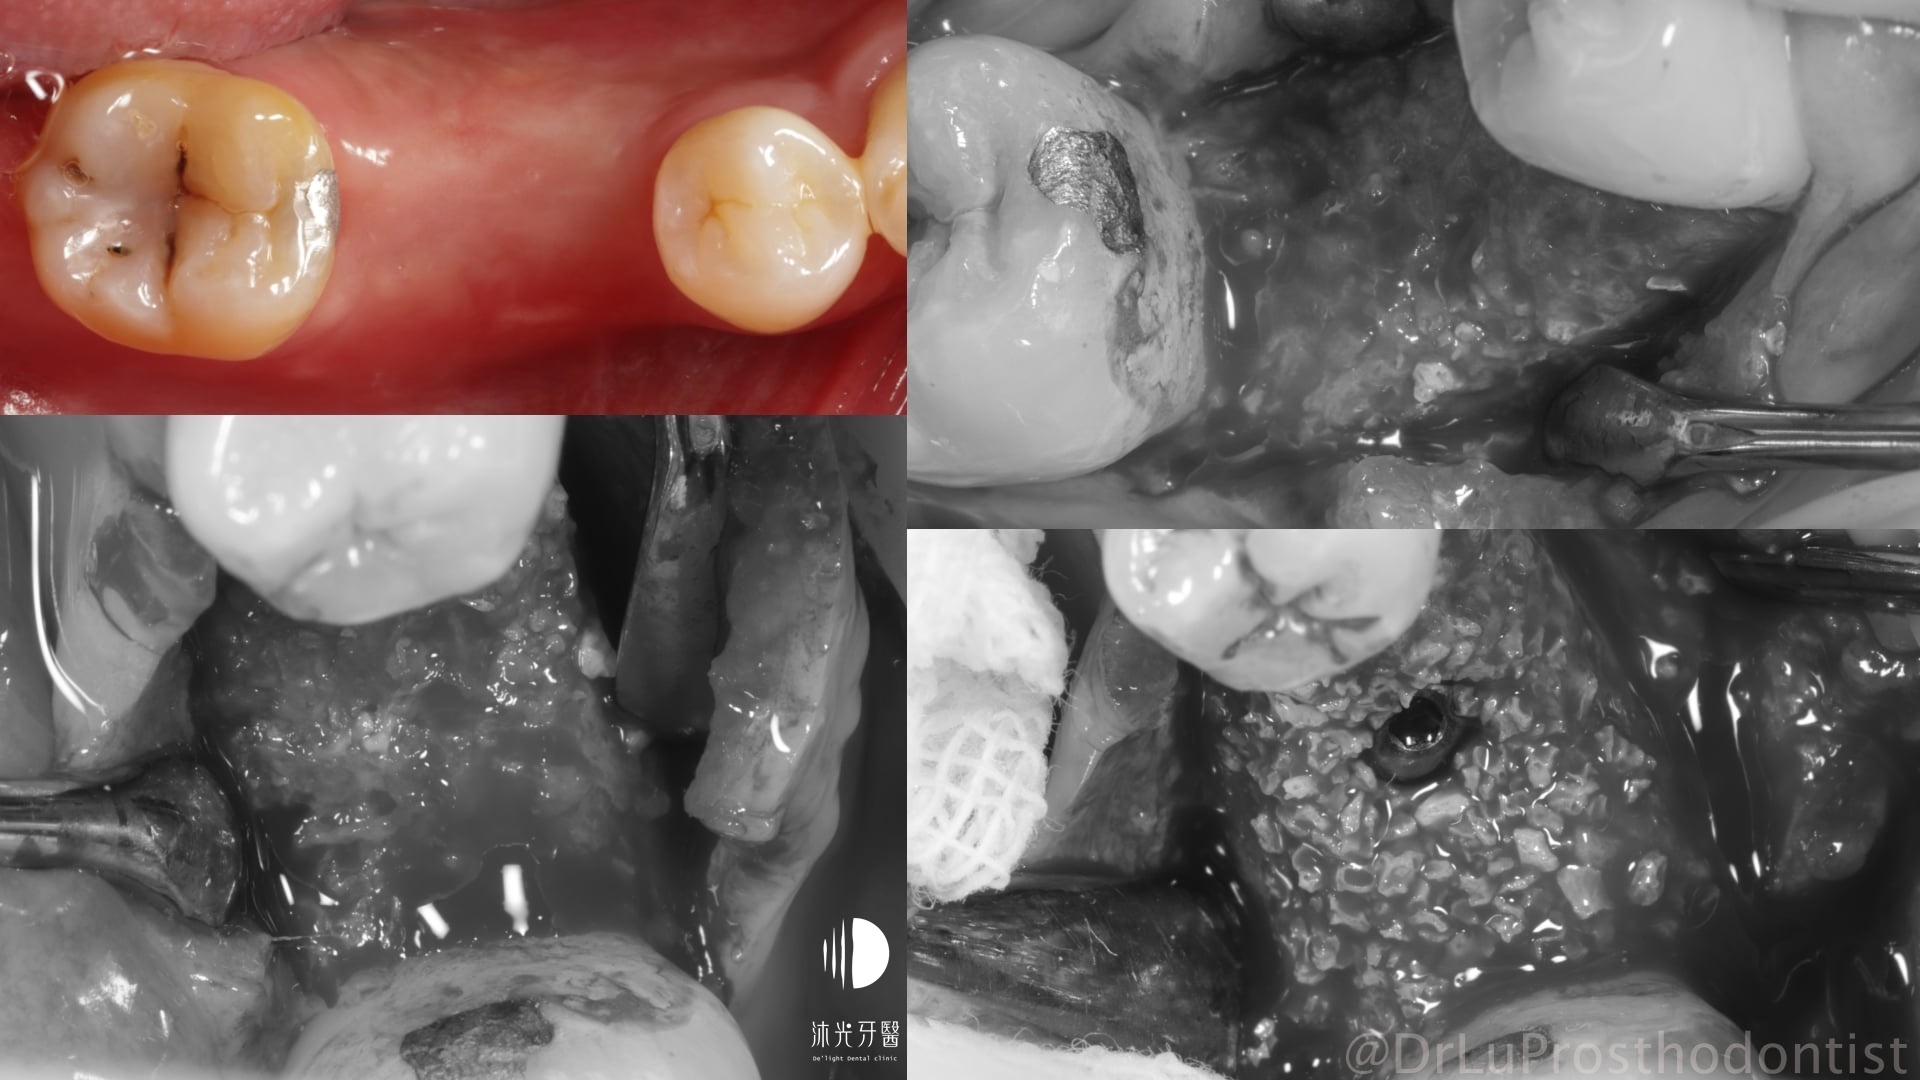

今天要分享的案例是一位近30歲的先生,右下第一大臼齒做完根管治療後以大範圍樹脂填補起來。來診一年多前不幸將牙齒咬裂了,當下疼痛不適但過了幾週後症狀緩解;偶而牙肉上會長膿包,但不會疼痛也不以為意,直到某天右下顎區域腫起來才趕快就醫。

X光及口內檢查可知齒槽骨長期發炎感染後嚴重吸收,拔牙當下整個拔牙窩就像一個大窟窿,裡面滿是感染形成的肉芽組織。整個植牙重建過程也沒辦法像一般患者這麼輕鬆(戲稱植牙重建的吃全餐),從拔牙清創補骨、植牙、補牙齦將缺失的組織一一重建好,才能完成接近自然牙狀態的植牙贋復。